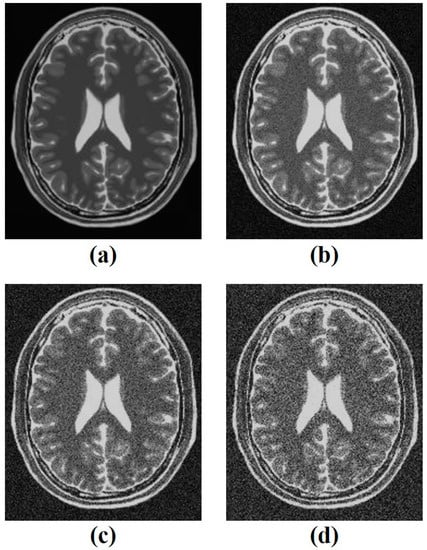

3.1. Simulation Study